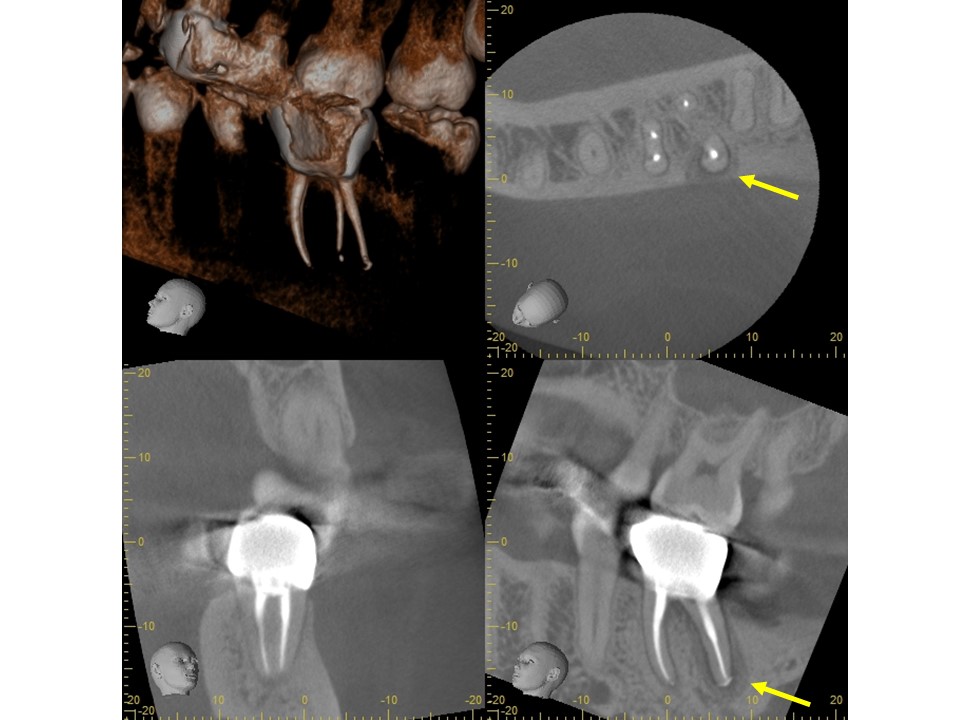

同CT画像。ファイバーコアで土台を補強し、仮歯の状態で3か月の経過観察を行った。初診時にあった歯の違和感は完全に消失したため、オールセラミックで補綴処置を行うこととした。